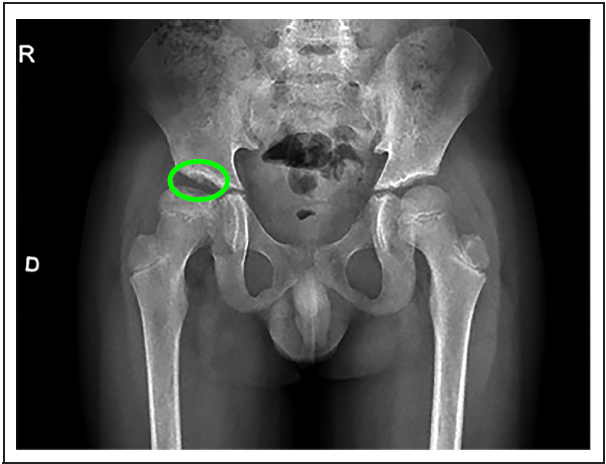

A los 9 años, en cita de control, menciona tener 15 días de evolución de claudicación a la marcha y dolor en cadera derecha, al examen físico se encuentra limitación funcional y dolor a la exploración, y por radiografías convencionales de cadera se evidencia necrosis del 30 % de la cabeza del fémur (figura 1). Ortopedia considera que no requiere manejo quirúrgico en ese momento y se le da manejo conservador. El manejo inicial se da con analgesia con ibuprofeno y transfusión de glóbulos rojos empacados. En radiografía de control 5 meses después ya se encuentra en etapa de remodelación. (figura 2)